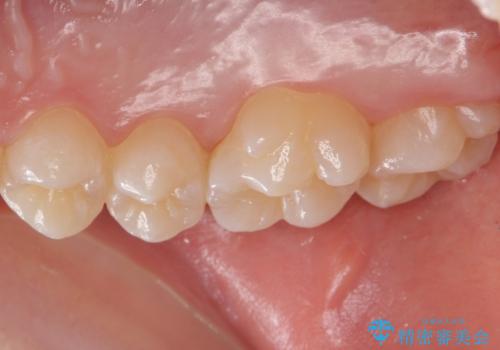

歯と歯の間の虫歯 セラミックインレーでの治療

- 検査の結果、レントゲン画像上で虫歯が確認されたため治療をしていくこととなりました。

白くて精度の高いものをご希望されたためセラミックインレーでの治療を行いました。

- 右上6 セラミックインレー 77,000円費用は治療当時の料金となります

小さな段差もないような適合の良い修復物は他の修復物に比べて今後の虫歯リスクを抑えることができます。